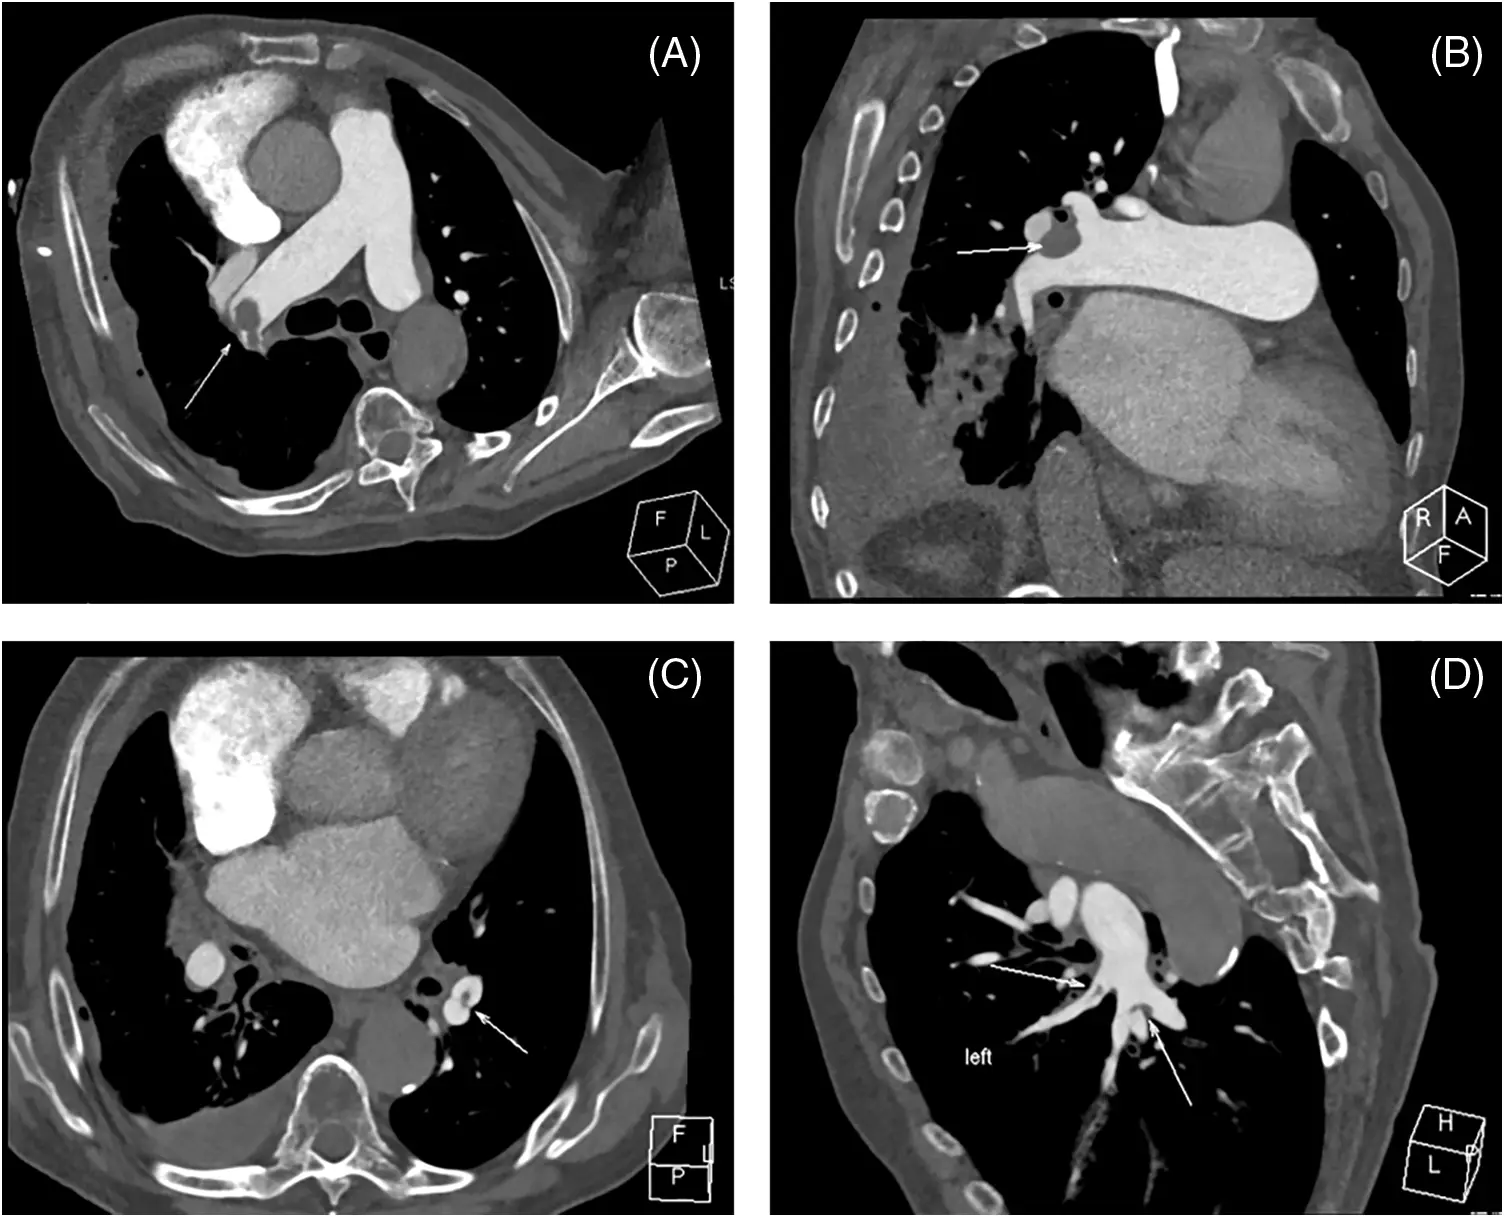

CTPA is a crucial diagnostic tool for pulmonary vascular disorders (Fig. 2). It is employed to diagnose CTEPH by detecting both direct and indirect symptoms, such as filling defects (which may include thrombus adhering to the vascular wall), webs or bands in the pulmonary arteries, PA retraction/dilatation, mosaic perfusion, and enlarged bronchial arteries [28,29]. A recent meta-analysis encompassed 10 single-center studies involving a total of 734 patients. The combined sensitivity, specificity, positive predictive value (PPV), negative predictive value (NPV), accuracy, and diagnostic odds ratio (DOR) of CTPA for CTEPH were found to be 0.98, 0.99, 0.94, 1.00, 0.96, and 292, respectively [28]. However, a basic limitation is that a negative CTPA test cannot rule out CTEPH because small vessel defects may be not found [27]. Nevertheless, CTPA can provide vital image guides for PEA to treat CTEPH [30].

Figure 2: CTPA images from chronic thromboembolic disease (CTEPH) patient. (A) Axial view demonstrates the occlusion in the pulmonary trunk, (B) Multiplanar reformation visualizes this occlusion, (C) Axial representation shows the occlusion in the left inferior pulmonary artery branch, (D) The occlusion in the said branch is further depicted via multiplanar reformation